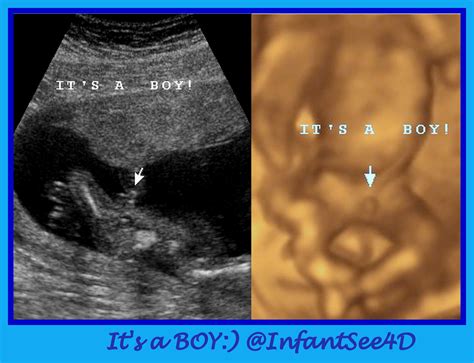

• Gender Determination: While it is still too early to determine the fetus's gender with certainty, some features may start to become visible. However, accurate gender determination typically occurs around 18-20 weeks.

• 13 week ultrasound pictures gender

• 13 weeks pregnant ultrasound girl

• 13 weeks ultrasound girl